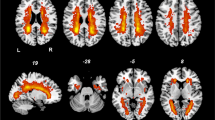

In our VBM analyses, the RLS1 patients had larger left superior occipital gyrus and precuneus when compared with the RLS0 patients. The GMVs of the substantia nigra (SN), mammillary bodies, and cuneus were decreased in the RLS1 group when compared with the RLS0 group (Fig. 3). Patients in the RLS1 group had increased GMVs of the superior temporal gyrus (STG), Brodmann area 38, and left insula compared with the control group, whereas there were decreases in the volumes of the splenium of corpus callosum (CC) and bilateral cerebrum sub-lobar white matter regions in this patient group compared with the controls (Fig. 3). The RLS0 group had increased volumes of the Brodmann area 22, right STG, and Heschl gyrus compared with the controls. The volumes of the frontal sub-gyral white matter and genu of CC were decreased in the RLS0 group compared with the control group (Fig. 3).

Brain morphological changes in migraine patients, RLS1, RLS0, and control groups in single T1-weighted MRI images (p < 0.001, uncorrected) via VBM. a Altered structural volumes in migraine and control groups. Yellow area shows volume increase; red area shows volume decrease in the migraine group. FSR, frontal superior right; TSR, temporal superior right; CC, corpus callosum; PIL, parietal inferior left; CaB, caudate body. b Altered structural volumes in RLS1 and RLS0 groups. Blue area shows volume increase; red area shows volume decrease in the RLS1 group. MIDB, midbrain; OSL, occipital superior left; OML, occipital middle left; SN, substantia nigra. c Altered structural volumes in RLS1 and control groups. Yellow area shows volume increase; red area shows volume decrease in the RLS1 group. SUB, sub-lobar; STG, superior temporal gyrus; INS, insula. d Altered structural volumes in RLS0 and control groups. Red area shows volume increase; yellow area shows volume decrease in the RLS0 group. FSWM, frontal sub-gyral white matter; HES, Heschl gyrus; BA 22, Brodmann area 22. L, left; R, right

Based on the VBM analyses, in comparison with controls, migraineurs had increased GMVs in the right STG, right superior frontal gyrus, Brodmann area 10, body of the caudate, and left inferior parietal gyrus. On the other hand, migraineurs showed GMV reductions in the pons and genu of CC when compared with the control group (Fig. 3).